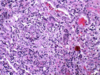

What does this histo show?

neutrophils filling the alveoli

capillaries sometimes break & you get hemorrhage in the sputum

pneumococcal pneumonia